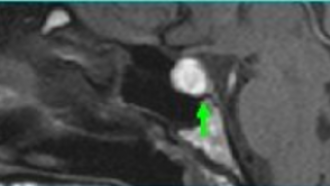

• El quiste de la bolsa de Rathke se origina de remanentes epiteliales de la bolsa de Rathke situados entre el lóbulo anterior y el intermedio de la hipófisis.

Durante el desarrollo embrionario, la bolsa de Rathke se forma como una depresión en el techo de la boca, eventualmente perdiendo su conexión a la faringe y dando lugar a la glándula pituitaria anterior.

Quiste

• Si en lugar de regresar la hendidura persiste y se agranda, puede formarse en un quiste de la bolsa de Rathke. La mayoría de estos quistes son pequeños, sin síntomas y se decubren de manera incidental y no precisan tratamiento.

En algunos casos, la acumulación continua de líquido puede hacer que el quiste crezca. A medida que crece, ejerce presión sobre las estructuras circundantes, incluyendo:

• Glándula pituitaria

• Quiasma óptico

• Hipotálamo

Síntomas: La gran mayoría son asintomáticos. Pero si crecen pueden presentar síntomas por compresión de estructuras cercanas como:

• Disfunción de la hipófisis

• Alteraciones visuales

• Dolores de cabeza…

Diagnóstico: La resonancia magnética es la prueba de elección.

Tratamiento: Para los quistes de la bolsa de Rathke asintomáticos, la observación a largo plazo. Si el quiste causa síntomas, o el diagnóstico es dudoso, el quiste puede requerir tratamiento quirúrgico. Se pueden abordar directamente utilizando el método endoscópico endonasal (EEE). Esta técnica, mínimamente invasiva enfoque permite a los cirujanos acceden al quiste a través del corredor natural de la nariz, sin hacer una incisión abierta